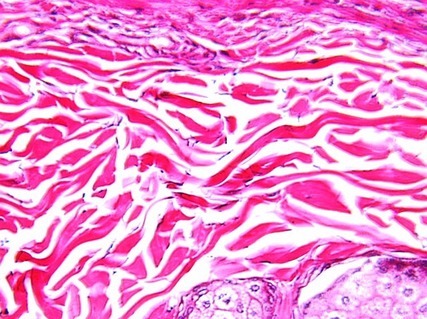

Reticular Dermis

In your slide, find the reticular layer of the dermis. The following photograph shows reticular dermis with elastic fibers (specially stained dark). This is dense, irregular connective tissue.